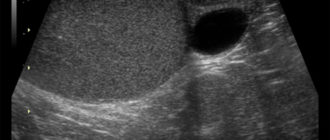

Узи яичек у мужчин: что показывает, как делают, подготовка и расшифровка статьи: Всего 20-30